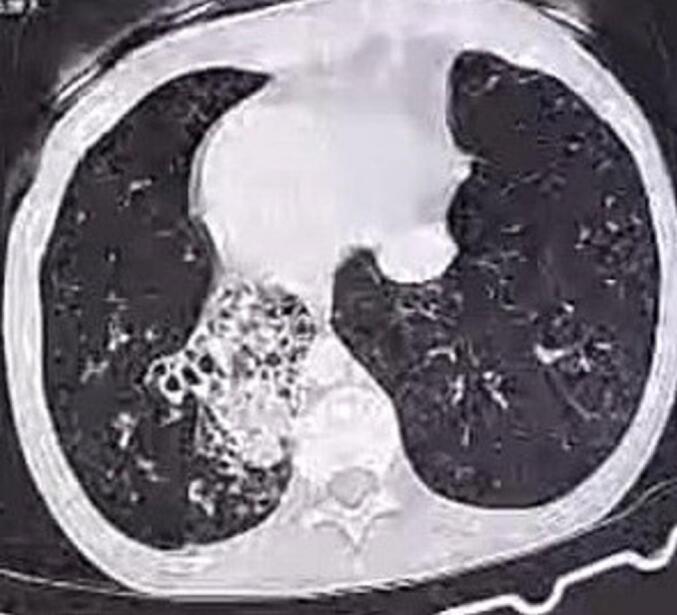

We present the case of a female patient with a history of recurrent respiratory infections since birth, treated with antibiotics and complicated by middle ear disease. Investigations revealed a rare presentation of air bullae associated with bronchiectasis. The patient was referred to our care and diagnosed with Kartagener syndrome, subsequently undergoing urgent surgical intervention, which contributed significantly to her overall improvement and the resolution of her thoracic condition.

我们报告一例女性患者,自出生以来有反复呼吸道感染病史,接受过抗生素治疗,并伴有中耳疾病。检查发现一种与支气管扩张相关的罕见肺大疱表现。该患者被转诊至我们处并被诊断为卡塔格内综合征,随后接受了紧急手术干预,这对她的整体康复以及胸部疾病的缓解有显著帮助。